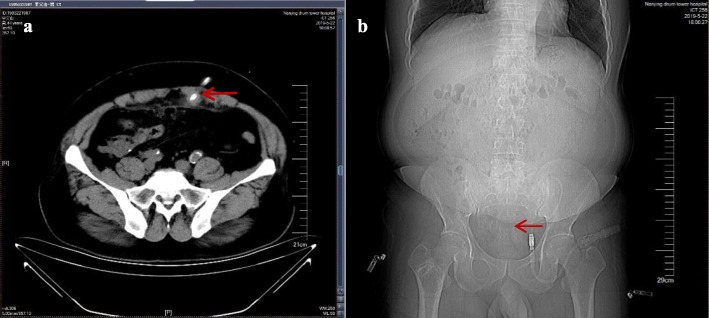

Abdominal computed tomography (CT) revealed inflammation in the abdominal cavity, extensive peritoneal calcification, and appropriate positioning of the peritoneal catheter, but intestinal perforation was not evident (Fig. 1). Peritoneal dialysate containing methylene blue reagent was injected into the abdominal cavity. After 2 hours, anal drainage was light blue (Fig. 2). Thus, an intestinal fistula was suspected. Colonoscopy revealed methylene blue at the area of the appendiceal orifice (Fig. 3), which confirmed the presence of a communication between the abdominal cavity and the bowel lumen. Peritoneal dialysis was discontinued and hemodialysis was initiated. The peritoneal catheter was removed by open surgery. No abdominal pain, abdominal distension, or other symptoms occurred during the follow-up period, which lasted a minimum of 3 months.

Fig. 1.

a, b Abdominal computed tomography and radiography showing proper catheter alignment